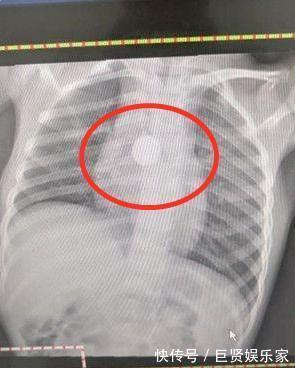

妈妈将自己的担心告诉医生,医生详细检查孩子之后建议拍个片子,再拍X光的时候,医生发现小女孩胸前有一个金属物,以为是孩子戴的项链,别让女孩的妈妈帮她摘下项链。妈妈听完医生的话完全懵了:''她没有戴项链啊,是不是其他的东西啊?''

后来经过仔细检查,发现孩子体内是一颗纽扣电池,而正是这一颗小东西,才导致小女孩这段时间没有胃口吃饭,甚至暴瘦,如果纽扣电池再不取出,就有可能给女儿造成更严重的伤害。回到家中,妮妮的妈妈对家中所有玩具进行了检查,发现其中一个玩具的纽扣电池少了一颗,想必是孩子出于好奇,而将纽扣电池误食。妈妈觉得非常愧疚,没有照顾好自己的女儿,险些让女儿受到生命健康的威胁。家里其实并不是完全安全的,因为家能够给我们安全感,所以很多父母都会忽略家中物品对孩子的威胁。那么父母该怎么做,才能防止孩子在家中受到伤害呢?1、不要给孩子买细小的玩具